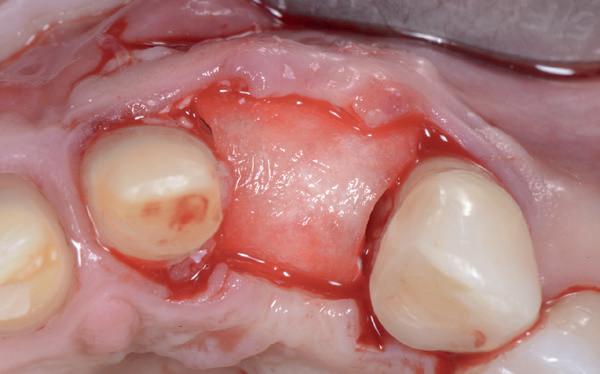

Zes maanden na extractie wordt het implantaat 37 geplaatst. Er is sprake van een goede genezing en de processushoogte en -breedte zijn behouden en opgebouwd. Ook is er zichtbaar gekeratiniseerd weefsel

gewonnen. De wond kan na het plaatsen van een healing abutment primair gesloten worden (Afbeelding 3a-3d).

In afbeeldingen 4a-c is het resultaat drie maanden na het plaatsen van het implantaat te zien. De genezing is volledig en de verwijzer kan de suprastructuur vervaardigen (afbeelding 4a-4c).